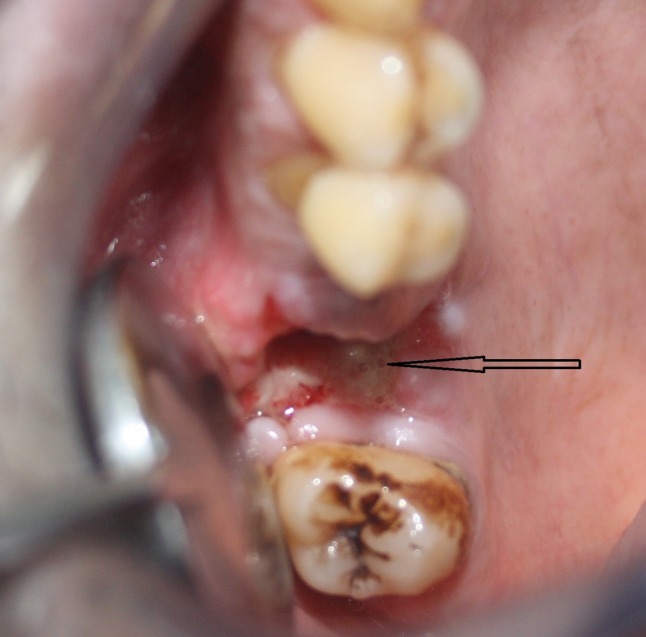

A 50 year old male patient came to the maxillofacial department OP complaining of drainage through the nose while taking water in the mouth. He had undergone extraction of upper right first molar elsewhere, 11 days earlier due to caries. On clinical examination the socket appeared traumatic and margins of the socket were not healed properly and communication to antrum of size 5 × 5 mm was noted (Fig. 1). OPG revealed an oroantral communication at the extraction socket (Fig. 2). PNS view showed generalized haziness of the right antrum which was suggestive of sinusitis (Fig. 3). The treatment plan was to do surgical closure after following proper antral regime and till clear lavage was achieved.

Fig. 1.

Oro antral fistula seen at upper right first molar traumatic extraction site